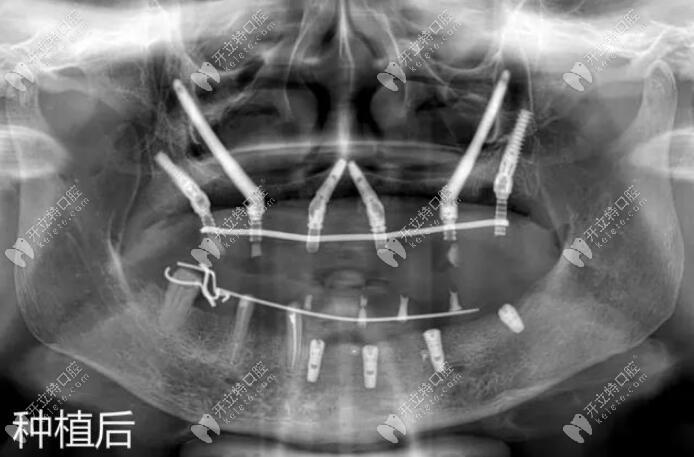

种植牙穿颧有没有后遗症?这是许多需要进行种植牙手术的人们所担心的问题。穿颧骨种植牙是一种比较复杂的手术,需要在颧骨(颧弓)骨质中进行植骨,以提供足够的支撑力。在穿颧骨种植牙的过程中,患者和医生都需要注意一些风险和注意事项。本文将从几个方面对种植牙穿颧有没有后遗症进行详细的阐述,帮助读者更好地了解穿颧骨种植牙手术。

穿颧骨种植牙虽然具有许多优点,但是也存在一定的风险。在进行穿颧骨种植牙手术前,医生需要对患者进行全面的检查,以确定患者是否适合进行此项手术。以下是穿颧骨种植牙的风险和注意事项:

穿颧骨种植牙的费用相对较高,因为这是一项比较复杂的手术,需要使用高端的设备和材料。手术的难度也较大,需要有经验丰富的医生进行操作。穿颧骨种植牙的费用在20000-50000元之间,具体费用还需要根据患者的具体情况进行评估。